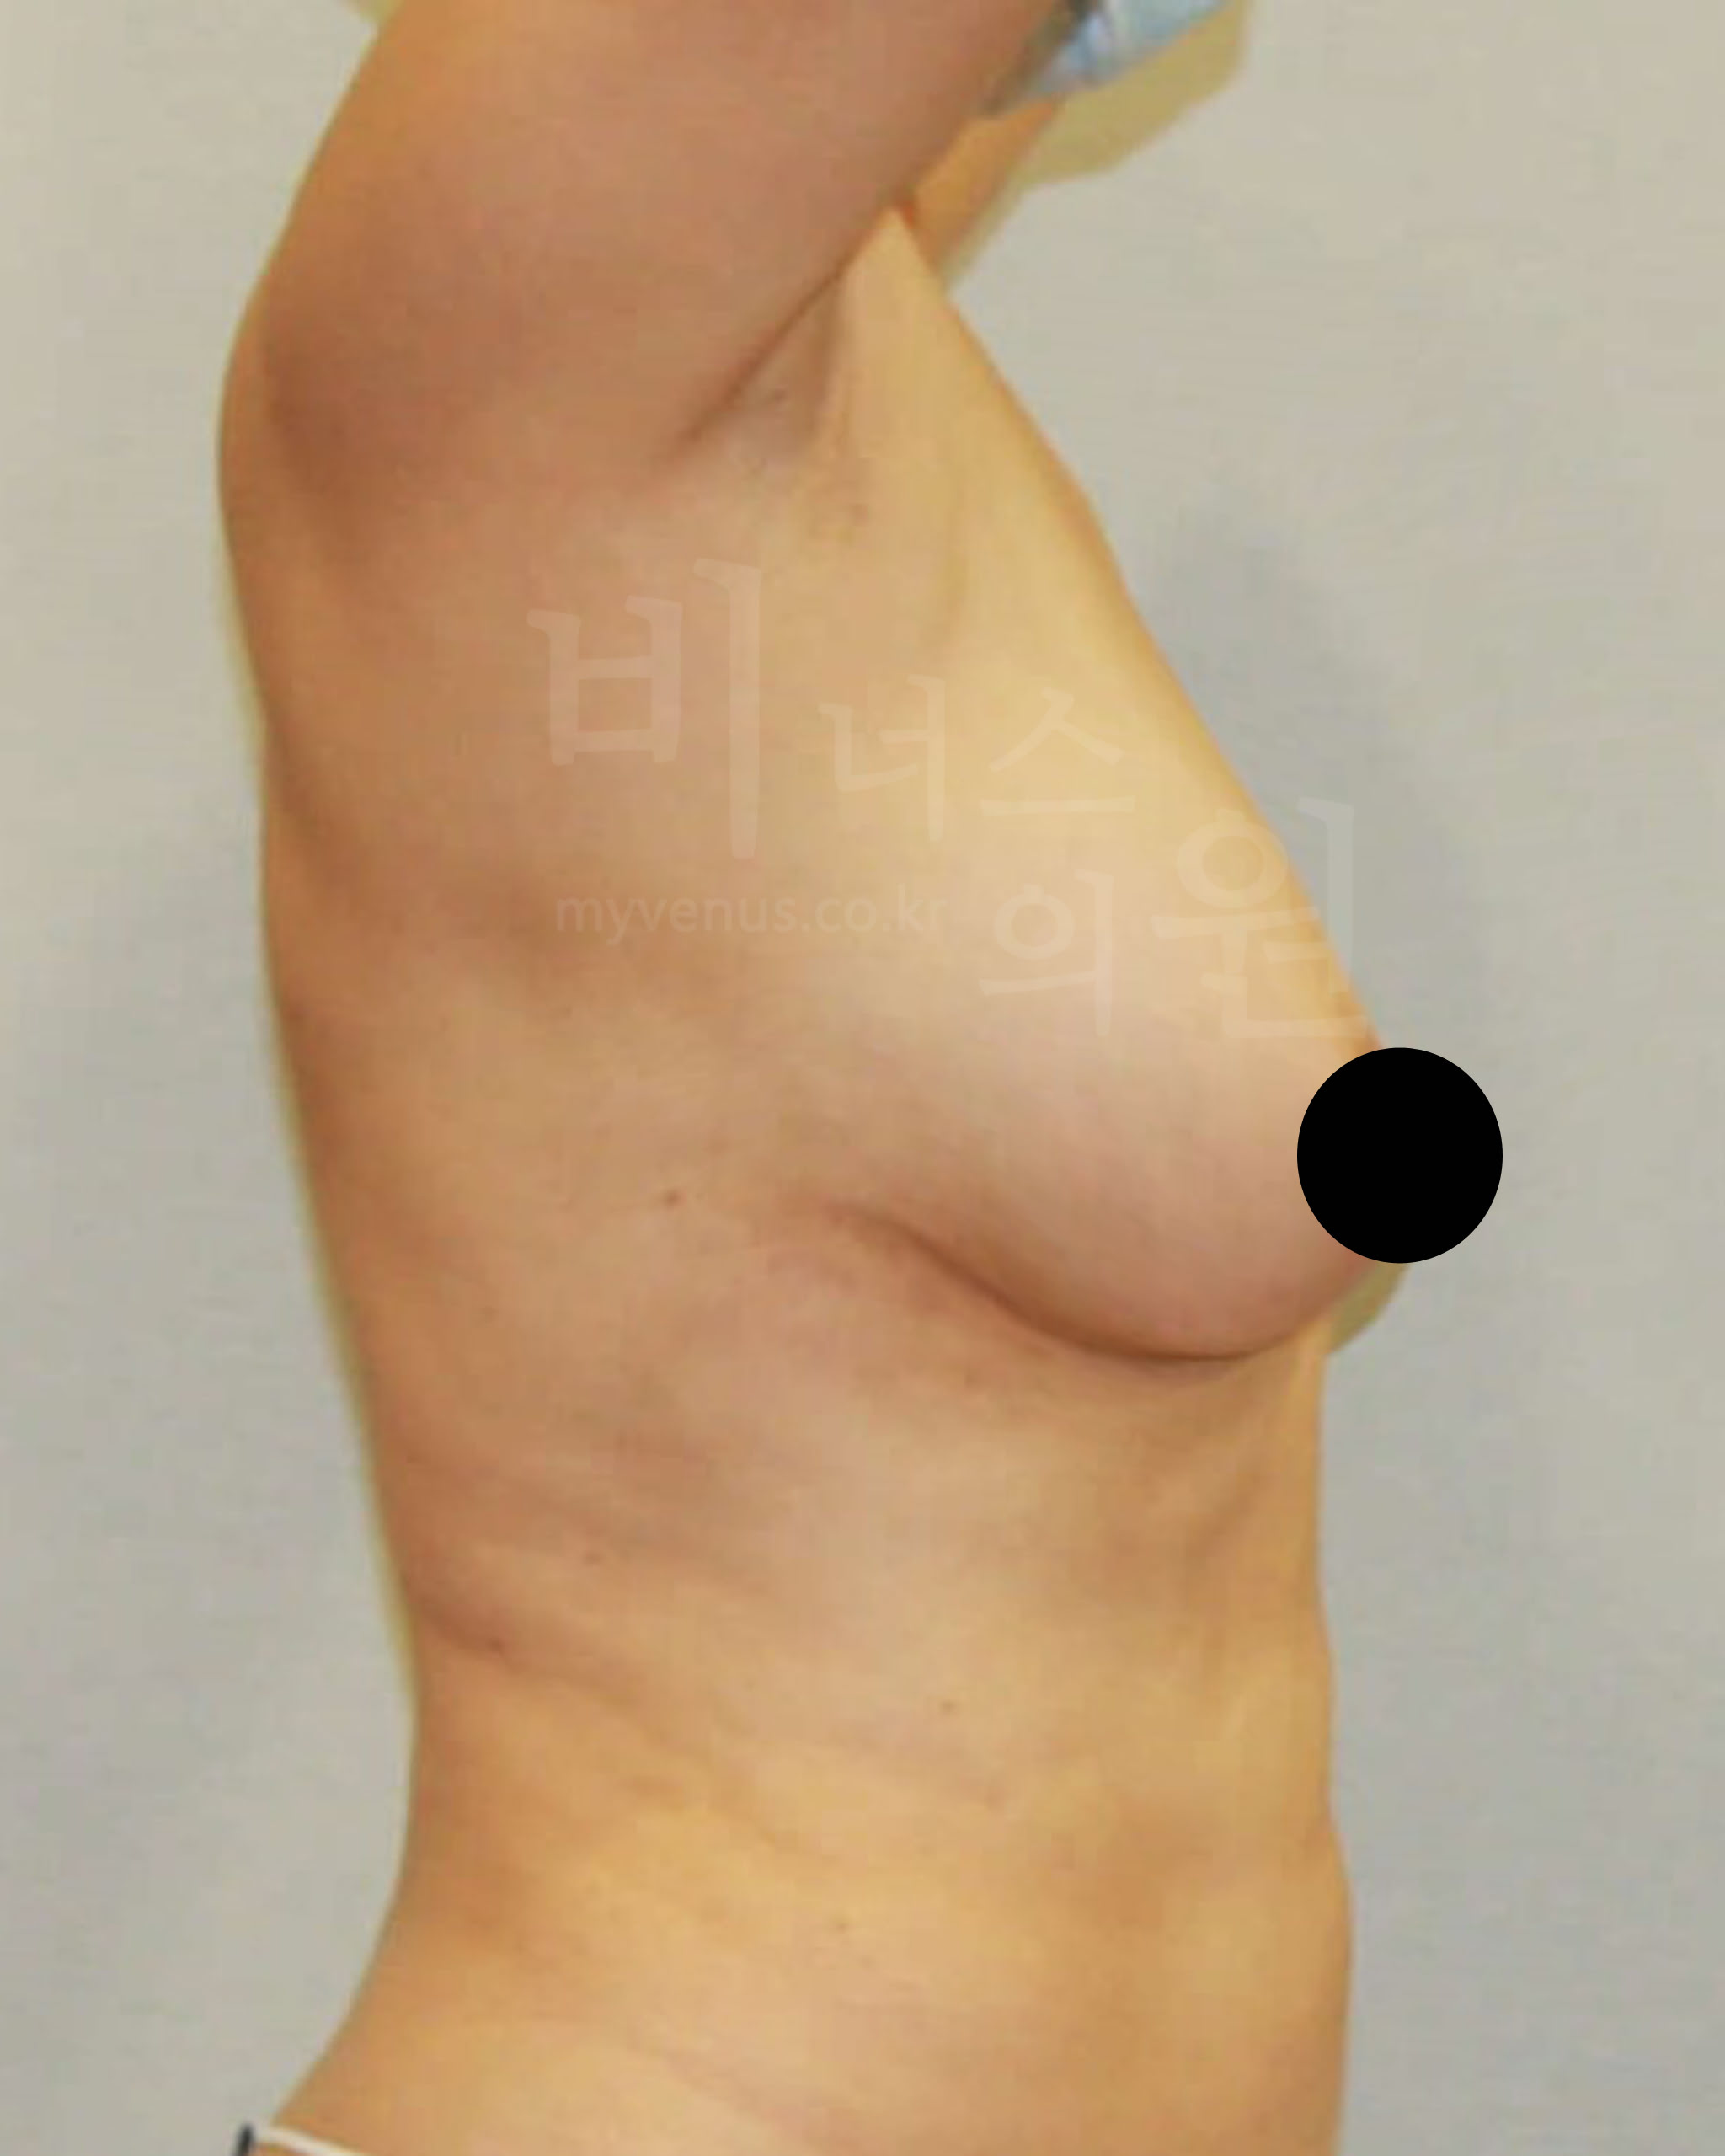

가슴축소 지방흡입 전 사진

탄력이 없어 힘 없이 가슴이 아래로 향한 모습

가슴축소 지방흡입 후 사진

피부 수축으로 리프팅과 탄력이 생긴 모습

가슴축 지방흡입은 절개를 하지 않아도 충분히 사이즈 감소와 처짐 없이 볼륨 업된 가슴으로 교정이 가능해요. 또한 유선을 건드리지 않고 지방만을 흡입하여 축소하기 때문에 젊은 여성분의 추후 모유수유에도 지장이 없어요. 멍, 붓기, 흉터, 부작용의 발생 없이 가슴이 자연스러운 모양으로 감소된 모습이에요.

수술 부위 - 가슴 축소, 부유방, 겨드랑이, 유방 옆구리 지방흡입

가슴축소 지방흡입 전 사진

처지고 무거워 밑으로 축 늘어져 있는 모습

가슴축소 지방흡입 후 사진

처지고 무거운 가슴이 교정된 모습

40대의 여성으로 사이즈 감소와 처짐의 교정을 위해 내원하셨어요. 탄력 있으면서 볼륨 있는 사이즈 감소를 원하셨어요. 가슴 축소, 부유방, 겨드랑이, 유방 옆구리 지방흡입으로 도움을 드리기로 했어요. 가슴 사이즈 감소로 무게감이 훨씬 줄어들어 보이며, 사이즈 감소와 탄력 있으면서 봉긋 업된 가슴이 되었어요.